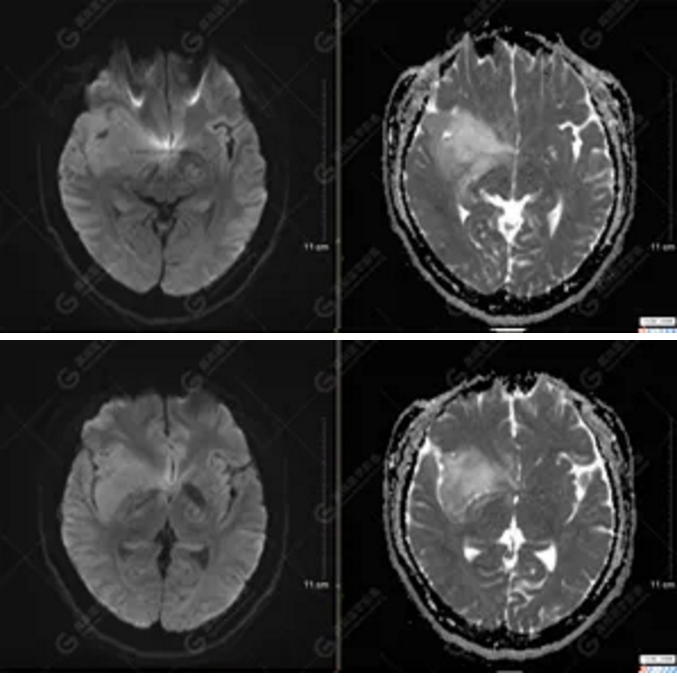

以上為DTI成像,圖1為皮質(zhì)脊髓束,圖2為胼胝體束,圖3為扣帶回束,圖4為額枕束。DTI成像示右側(cè)額枕束前部明顯受壓、部分未見(jiàn)顯示;胼胝體束、雙側(cè)扣帶束、皮質(zhì)脊髓束及左側(cè)額枕束形態(tài)可,纖維束未見(jiàn)明顯破壞,未見(jiàn)明顯稀疏減少。

2.DTI成像示右側(cè)額枕束前部明顯受壓、部分未見(jiàn)顯示。